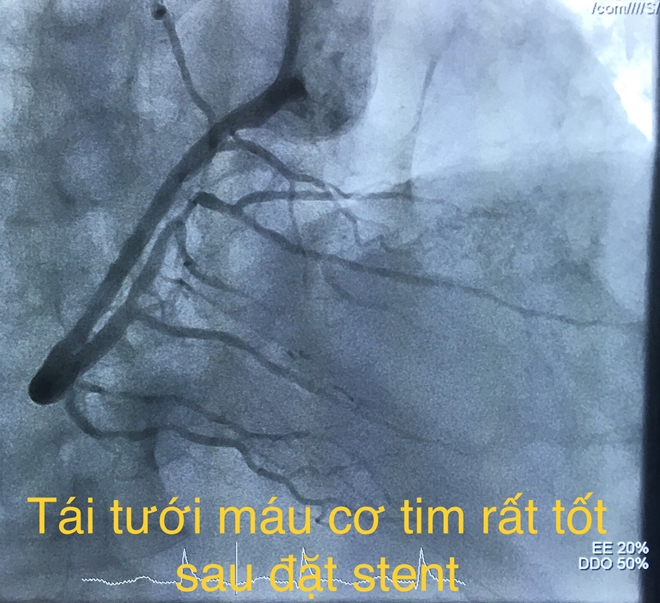

Sau can thiệp tái thông, huyết động của bệnh nhân cải thiện rõ, sinh tồn ổn định và được đưa về Khoa Hồi sức tích cực – Chống độc để theo dõi và hồi sức nội khoa. Hiện bệnh nhân tỉnh, tiếp xúc tốt, dấu hiệu sinh tồn ổn định.

Và sau khi được tái thông.